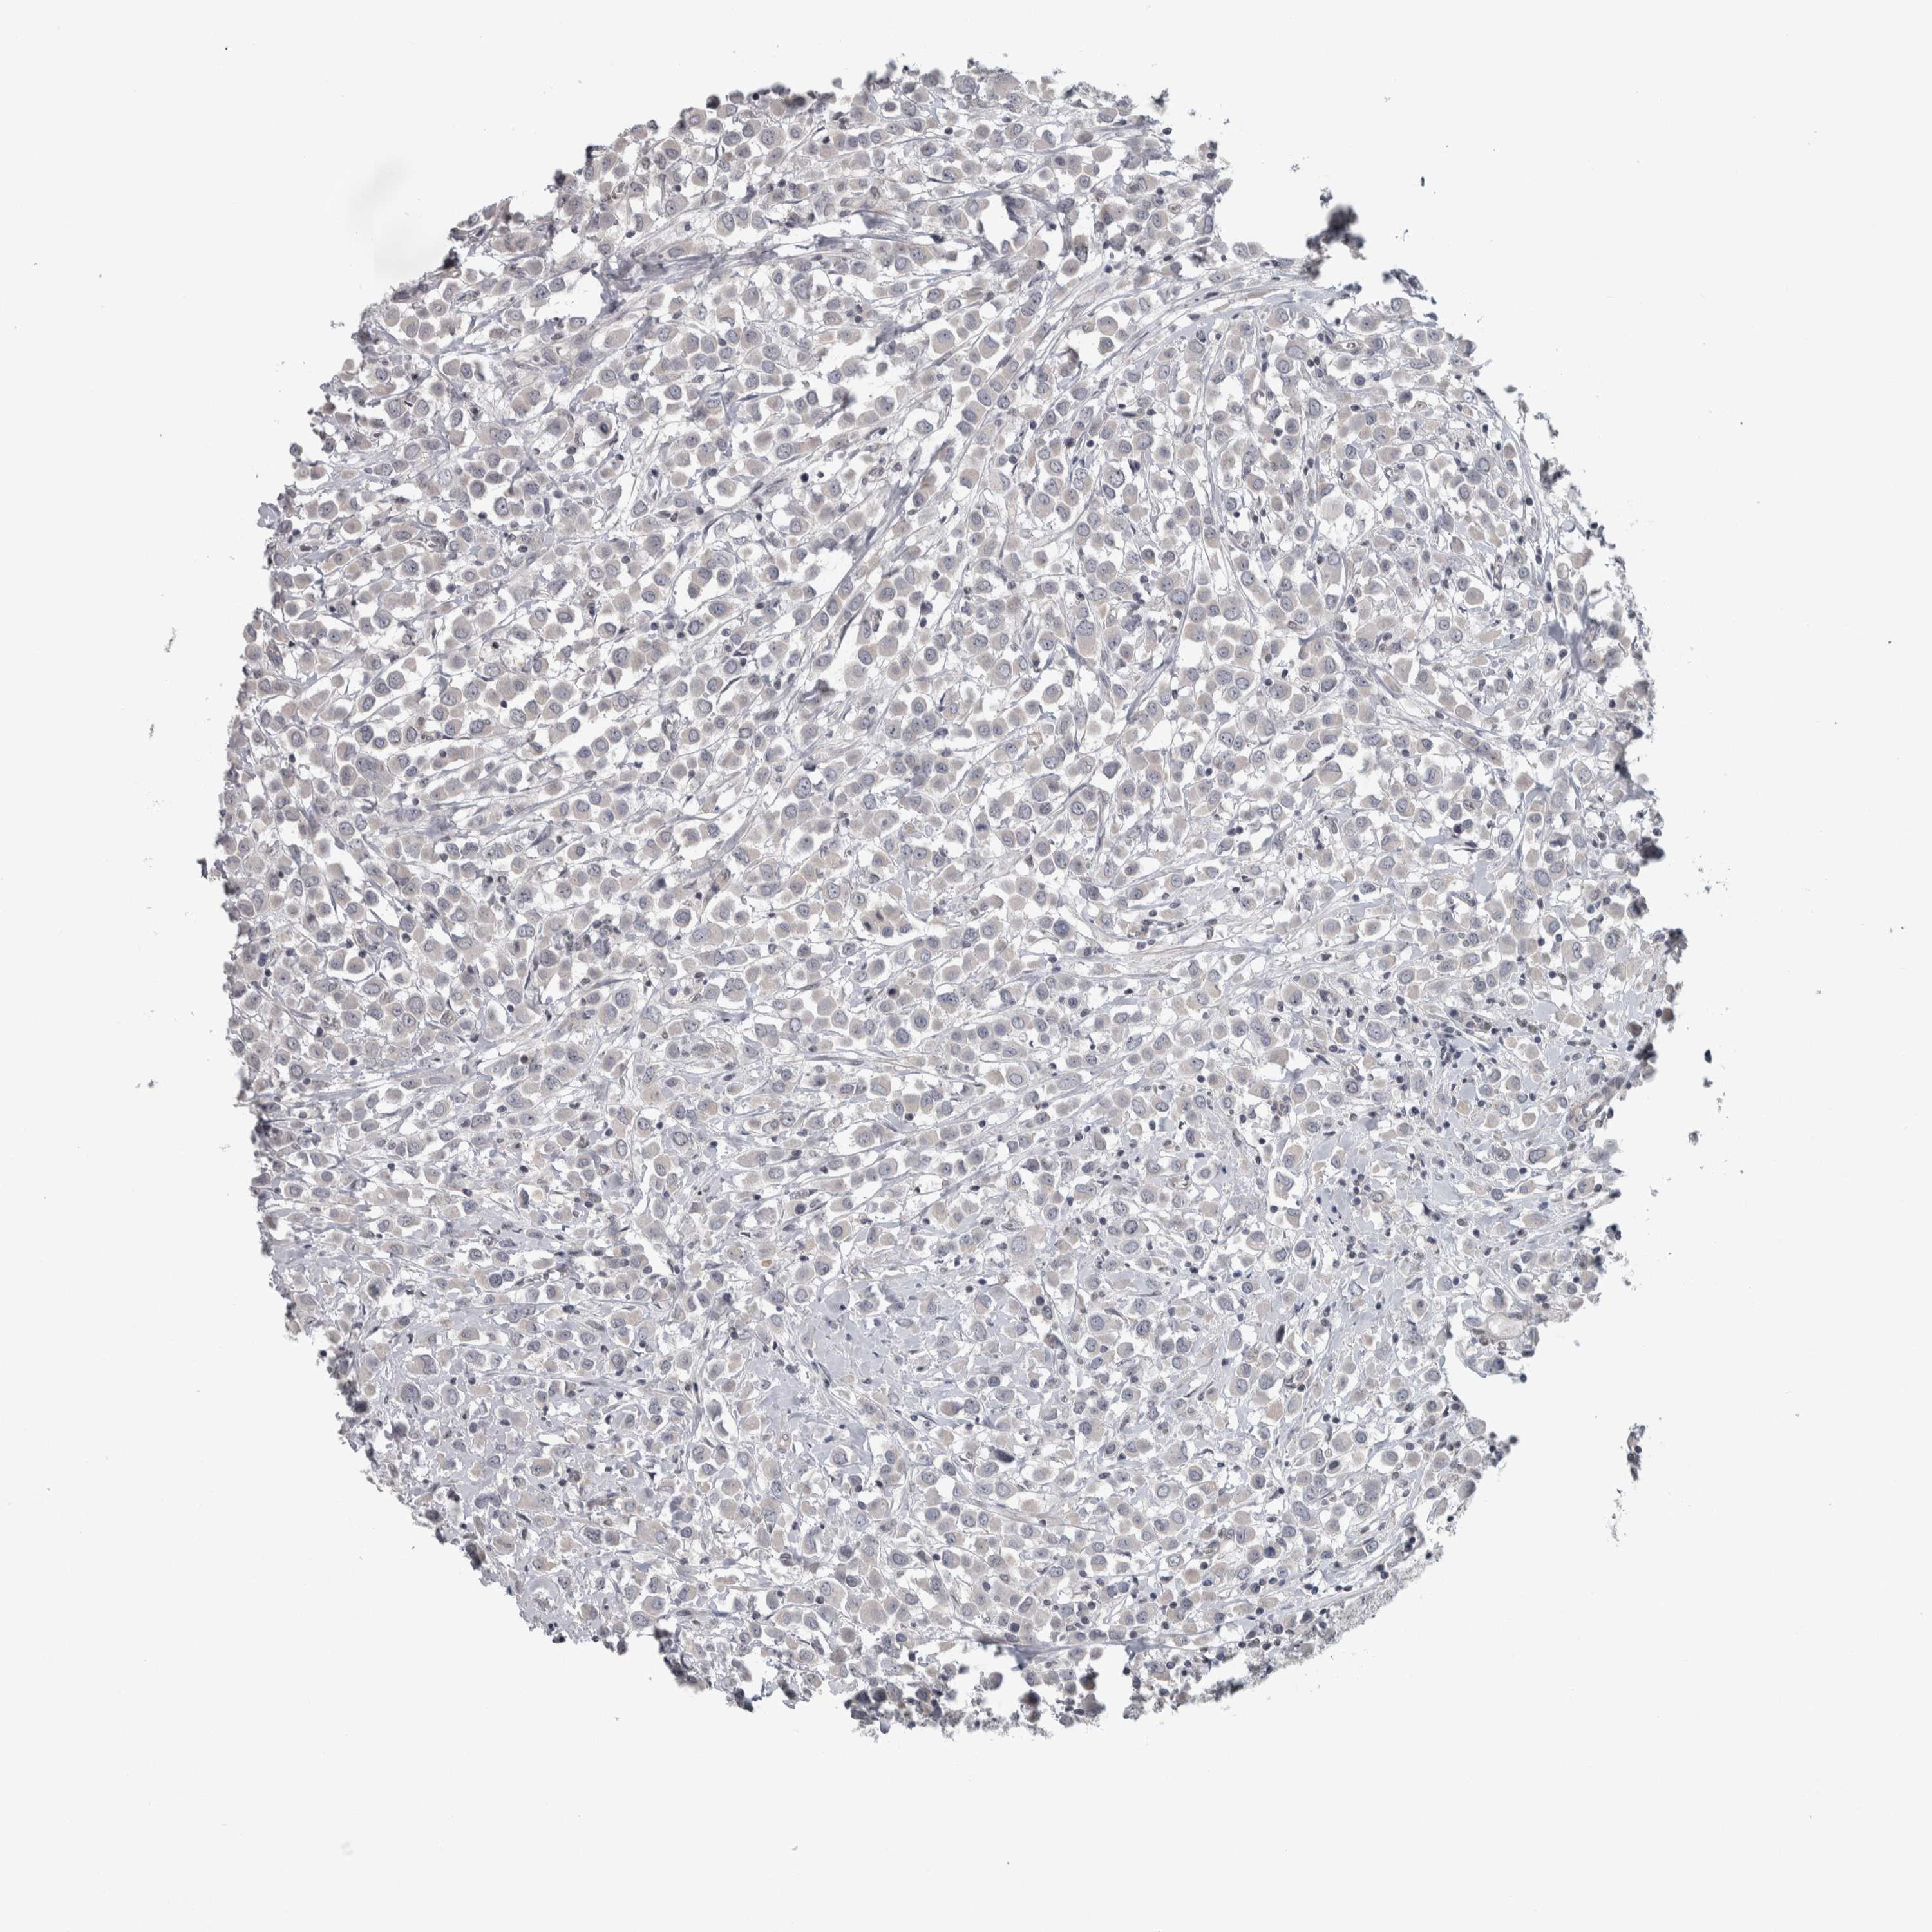

CANCER BREAST CANCER Show tissue menu

BRCA TCGA BRCA VALIDATION PROTEIN EXPRESSION